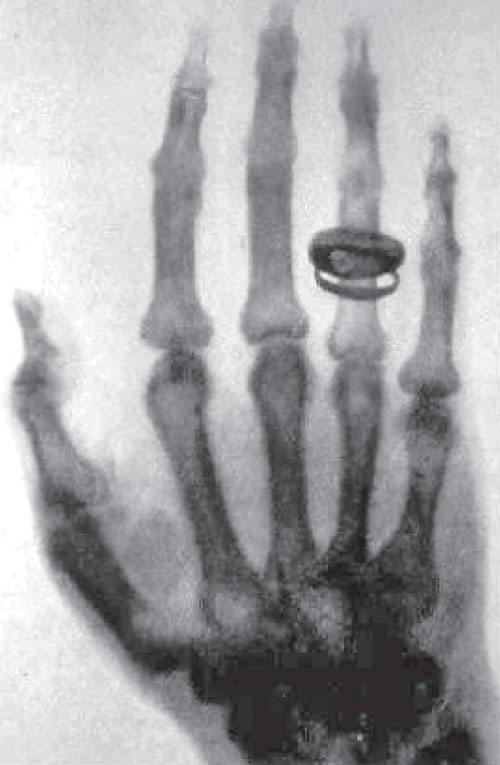

"I have seen my death!"

— Anna Bertha Röntgen, upon seeing the X-ray of her hand, December 22, 1895

Röntgen named these unknown rays "X-rays." On December 22, 1895, he took the first medical image in human history—an X-ray of his wife Anna Bertha's hand. When Anna saw the X-ray showing her hand bones and wedding ring, she exclaimed in shock: "I have seen my death!" This photograph marked the beginning of a new era in medical diagnosis.